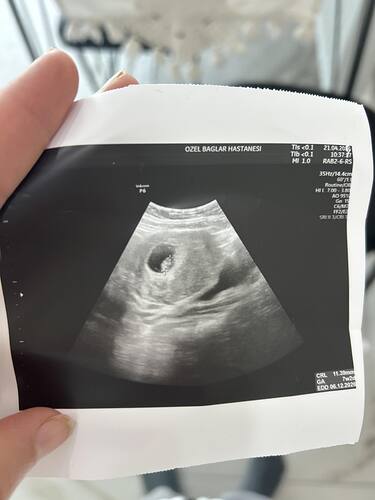

Erkek bebek canım aşağıdan tutunmuş ve kesesi yuvarlak biraz daha büyüsün tekrar atarsin tekrar yorumlarım

Erkek bebek gibi canim

Erkek olabilir